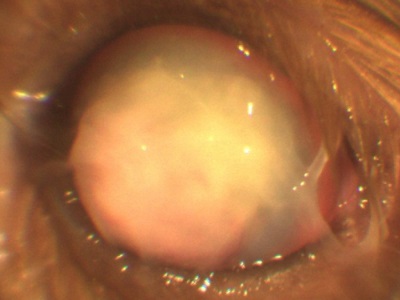

Opacifierea cristalinului (cataractă) este adesea interpretată ca un „spin“. Se sigilează nucleul de lentile, de asemenea, pare tulbure.

Cataracta poate avea loc din motive genetice (cea mai comună cauză), ca urmare a diabetului zaharat, penetrante leziuni corneene, radiații ionizante, și așa mai departe. În funcție de gradul de maturitate a algoritmului de acțiune a cataractei selectat. Cel mai eficient mod de a trata cataracta - o intervenție chirurgicală. Distrugerea substanței opace transportate, eliminarea ei și implantarea lentilelor speciale.

Pentru a distinge cataractă și etanșează miezul necesar să se efectueze examinarea ochilor: biomicroscopie, oftalmoscopie, etc. Pentru a face acest lucru, prezența echipamentului oftalmic este necesar.!